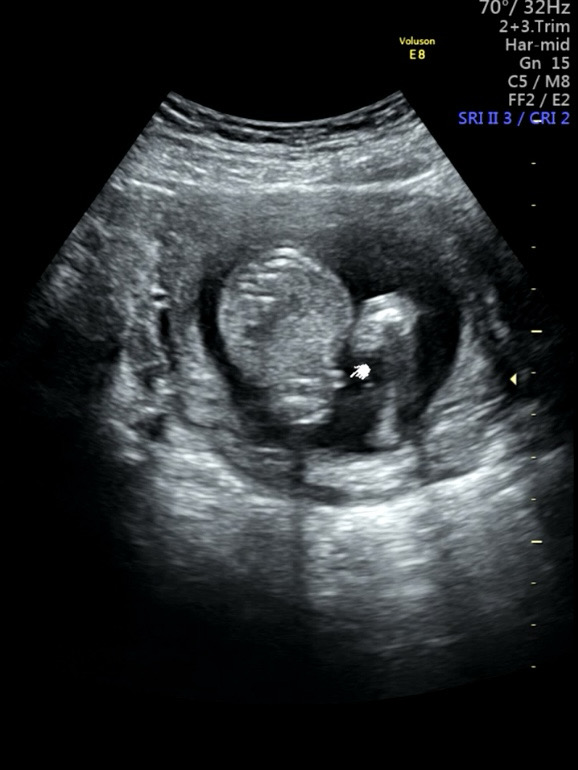

혹시 뽀기 성별 알 수 있을까요?

원장님이 집에가서 연구해보라고 하시는데 ㅠㅋㅋㅋ 첫 아이라 아무리 봐도 모르겠네요 ㅠㅠㅠ 성별보기 고수님들 도와주세요!!!! 딸일까요 아들일까용?

딸같아용~저렇게 두줄보이면 딸이라고 하더라구용!

아들같아요~